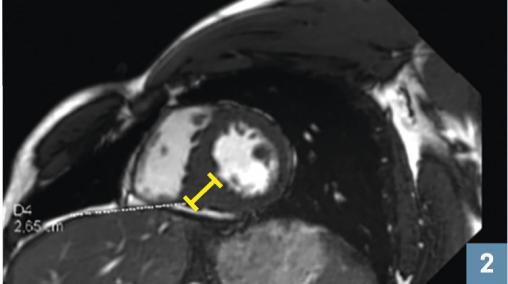

L’IRM de 2019 montre une cardiomyopathie hyper- trophique avec un septum mesuré à 26 mm en inféroseptal.

Le diagnostic repose sur l’échographie ou l’IRM : hypertrophie asymétrique à prédominance septale sans dilation du VG, après avoir exclu les autres causes (cardiopathie hypertensive, maladie de surcharge, non compaction ventriculaire, valvulopathie aortique, cœur d’athlète). Une enquête familiale est souhaitable (dépistage des apparentés au 1er degré).